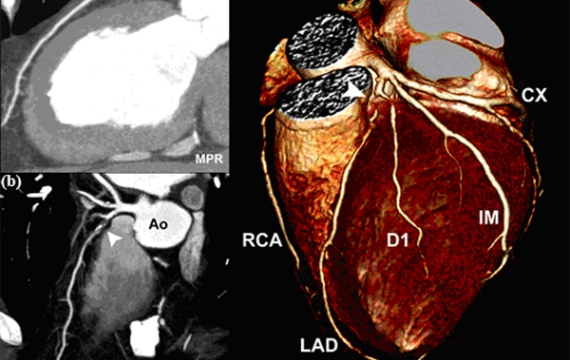

Resonancia magnética (RM) cardíaca

Es la mejor manera de tomar fotografías de tu cuerpo y medir el rendimiento de tu organismo. Dicho método se popularizó tanto debido a que elude el uso de radiación. Emplea un imán con el fin de sacar fotografías del corazón en movimiento durante más de 30 minutos.

Por supuesto, existen ciertos aspectos que debes tener en cuenta en los que respecta a su aplicación:

- Los niños menores de 6 años deben usar anestesia.

- Los niños mayores de 6 y adultos jóvenes deben hacer una prueba de 60 minutos (pueden dormir o ver una película durante todo este tiempo).

- Los bebes de meses deben someterse a la prueba ‘comer y arroparse’ (para evitar el uso de anestesia).

- Las personas que tienen metales en su cuerpo no pueden someterse a este tratamiento debido al imán.

Conociendo los tipos de pruebas cardiológicas más comunes, ¿qué estás esperando para plantearlas a tu médico? El cardiólogo es el único que debe determinar a qué pruebas debes someterte, ya que hay muchos factores que debe analizar.